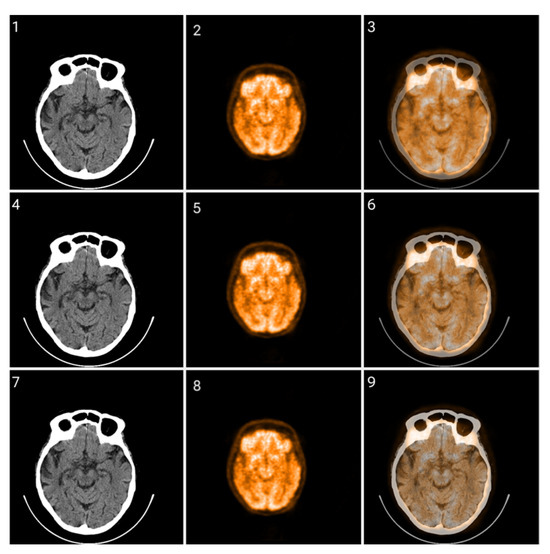

3.1. CIT Application

3.2. Colormap Folding Application